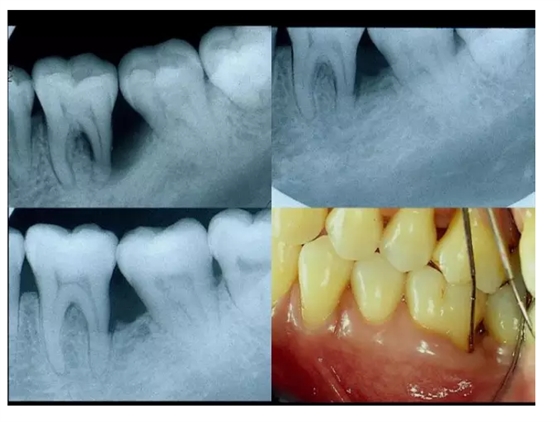

【牙科知識(shí)】牙周病相關(guān)手術(shù)圖解,非醫(yī)學(xué)專業(yè)勿點(diǎn)